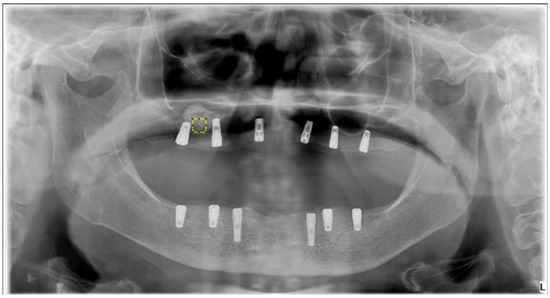

2.5. Fractal Dimension Analysis

FD analysis was performed to quantitatively assess trabecular bone complexity in grafted and physiologic regions. All operations were carried out using ImageJ v. 1.54 (National Institutes of Health, Bethesda, MD, USA), and FD was calculated via the FracLac plugin using the box-counting method. For each case, 25 × 25 pixel ROIs were manually defined over trabecular bone in the postoperative sinus lift and tuberosity regions. Figure 2 shows the selection of representative ROIs on a postoperative panoramic radiograph, highlighting standardized regions from both the grafted sinus floor and the native tuberosity site. The images were preprocessed following a standard protocol to isolate trabecular structures and enhance structural clarity prior to FD extraction. When necessary, the panoramic images were rotated to achieve optimal ROI alignment. The magnifying tool was used to enlarge the target area, and the defined ROI was cropped and duplicated for further processing. To reduce grayscale noise caused by soft tissue density and to enhance the visibility of trabecular patterns, a Gaussian blur filter (σ = 35 pixels) was applied to the duplicated image. The blurred version was then subtracted from the original, yielding a high-contrast image. A gray value of 128 was subsequently added to normalize intensity, followed by binarization to convert the image to black and white. As illustrated in Figure 3, this preprocessing sequence included erosion and dilation to clean the image and refine trabecular outlines, followed by inversion and skeletonization to reduce trabecular structures to their linear representations, thereby enabling clearer visualization of bone architecture. In the final step, the FD was calculated using the “Fractal Box Count” function under the Analyze menu. The skeletonized ROI was overlaid with square grids of increasing box sizes (2, 3, 4, 6, 8, 12, 16, 32, and 64 pixels). For each box size, the number of occupied boxes was recorded. A log–log plot of box count versus box size was constructed, and the slope of the best-fit regression line was taken as the FD value. The same analysis was independently repeated for each ROI in each patient, including both grafted and control regions. All measurements were performed twice by the same examiner, and intraobserver reliability was evaluated using intraclass correlation coefficients on a 20% sample.

Figure 2. The yellow square represents a manually selected 25 × 25 pixel Region of Interest (ROI) from the grafted sinus floor region. The ‘L’ represents the left side. These standardized ROIs were used to extract FD values, enabling a comparative assessment of trabecular bone complexity between grafted and physiologic sites.